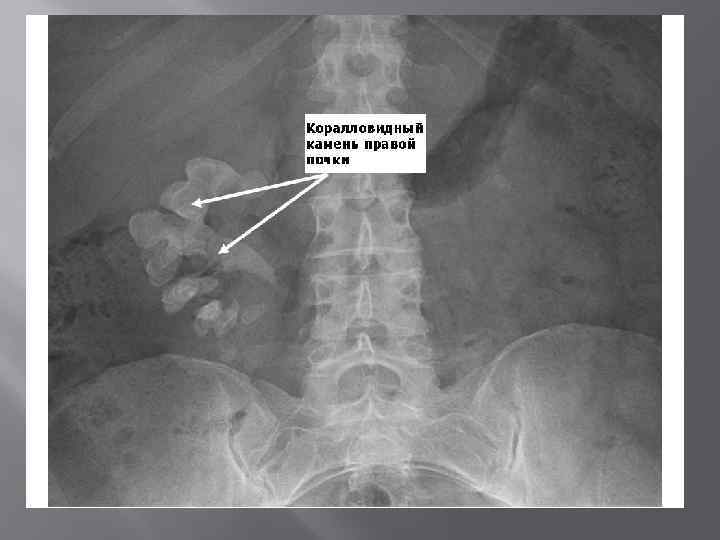

Коралловидные камни